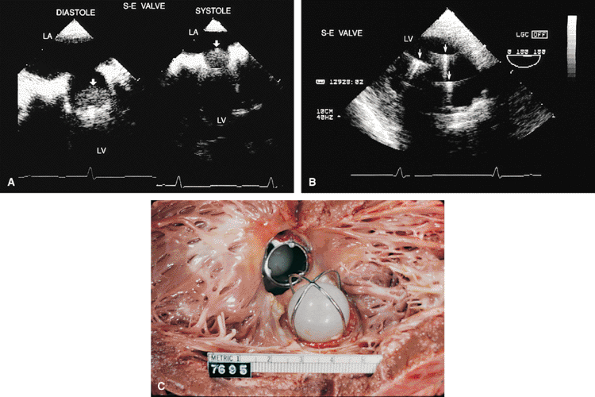

FIGURE 5.10. Starr-Edwards prosthesis: normal. A. The rounded poppet (arrows) is seen in the open position in diastole and in the closed position in systole. B. Transgastric view shows the three prosthetic struts (arrows) together with the resulting reverberations imaged in short axis. C. Gross specimen shows Starr-Edwards prostheses in the aortic and mitral positions. LA, left atrium; LV, left ventricle. |